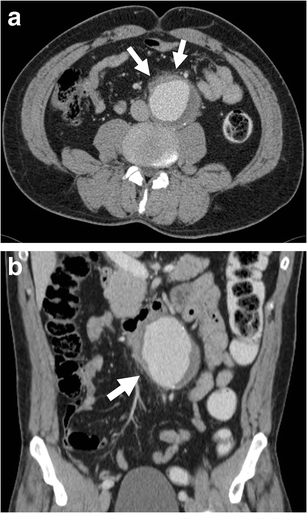

Periaortic stranding. a Axial and b coronal enhanced CT of a 51-year-old man with abdominal pain shows stranding of periaortic fat (white arrows) before any retroperitoneal haematoma can be seen